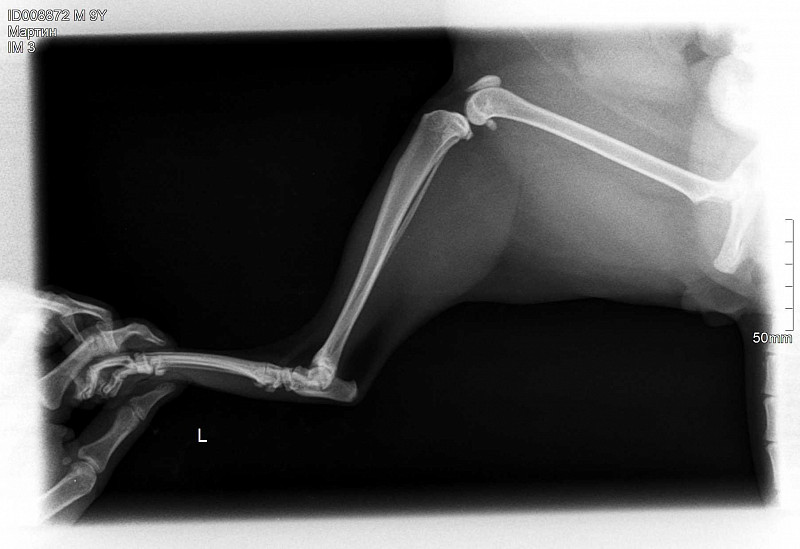

Рентгеновские снимки перелома лапы у кота: диагностика и лечение